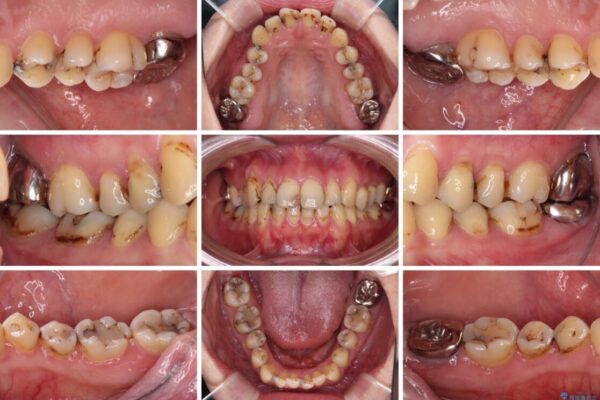

上下前歯や奥歯の虫歯治療を希望して来院された患者様です。

全顎的にむし歯が多く、根管治療の必要な奥歯や、審美的に気になっている前歯を中心にオールセラミッククラウンにて補綴治療を行うこととしました。

上顎前歯は歯肉退縮により歯根が露出していたため、事前に歯肉移植術により根面被覆を行い、その後にオールセラミッククラウンを装着することとしました。

治療途中

• むし歯だらけの前歯をオールセラミッククラウンできれいに 治療途中画像